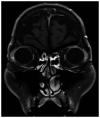

Metastatic choroidal carcinoma is rare and generally has a poor prognosis. The present case report describes a case of choroidal metastasis from distal cholangiocarcinoma, which was successfully managed using stereotactic radiotherapy (SRT). A 67-year-old Japanese man underwent pancreaticoduodenectomy for distal cholangiocarcinoma. The pathological stage was T2N0M0 stage IIA, according to the Union for International Cancer Control 8th edition. After surgery, the patient received adjuvant chemotherapy with oral TS-1® for 1 month. A total of 2 months after surgery, the patient was readmitted to hospital due to decreased visual acuity. Fundoscopy revealed a macular hole in the right eye that accounted for the decreased visual acuity. Additionally, Goldmann three-mirror contact lens examination revealed a 4-mm choroidal mass with a yellowish color situated at a considerable distance from the optic nerve. Magnetic resonance imaging revealed an enhanced choroidal mass. Based on the findings of ophthalmologic examinations and the patient's history of cholangiocarcinoma, they were diagnosed with choroidal metastasis from distal cholangiocarcinoma. SRT was administered at a total dose of 40 Gy divided into 8 Gy fractions. A total of 1 year after SRT, the patient achieved complete remission without decreased visual acuity. The patient remains alive and in good health without recurrence, 4 years after the diagnosis of choroidal metastasis. To the best of our knowledge, this is the second reported case of intraocular metastasis from cholangiocarcinoma. In conclusion, SRT may provide an opportunity to control metastatic choroidal carcinoma without decreasing visual acuity.